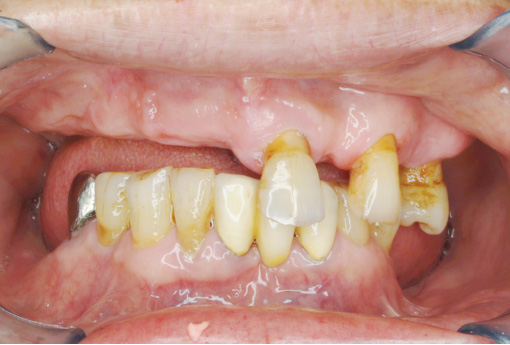

- BEFORE

- AFTER

-